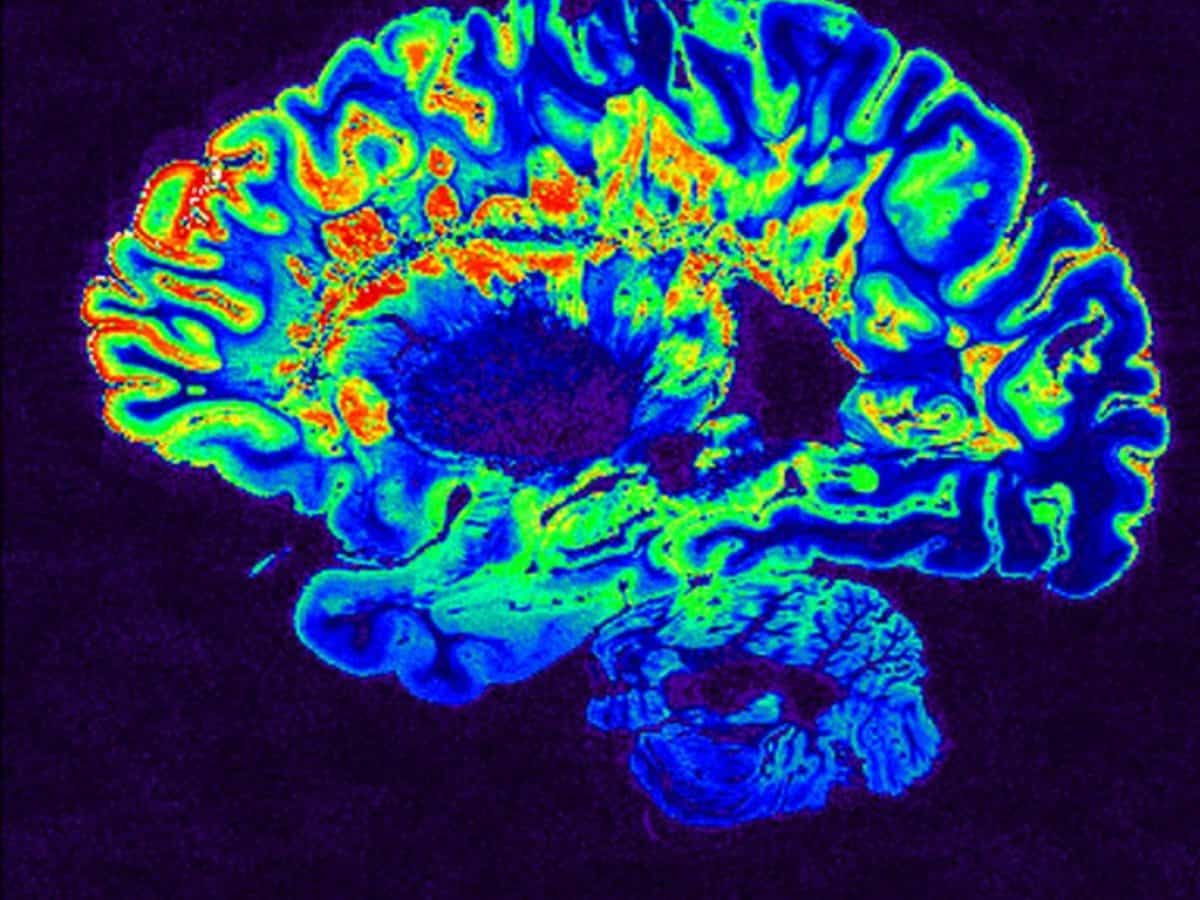

Σκλήρυνση κατά πλάκας: Επιστήμονες εντόπισαν δύο νέους υποτύπους της νόσου